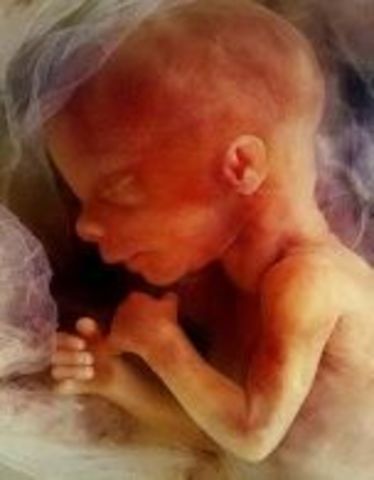

• Week 24: Breathing

Week 24: Breathing

By this week, the baby is 12 inches long and weighs 1.3 pounds. The baby is now practicing how to breathe since branches of the respiratory tree are forming in its lungs. It is currently being covered by hair. The baby is beginning to look like an actual baby with increasing facial features.

Facts: The child is now gaining 3 ounces a week

-36% of babies can survive premature birth at 24 weeks